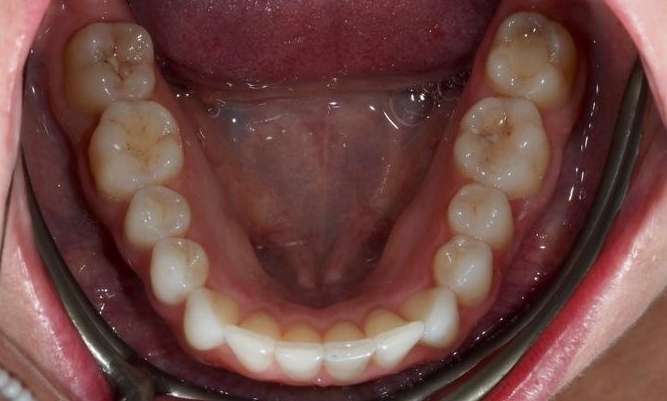

This patient presented with concerns about the damage his teeth had sustained from his bite and previous habits. His lower teeth had caused erosion and wear on the palatal surfaces and incisal edges of his upper front teeth. He was also concerned about the crowding of the lower front teeth. His primary goal was to create a more protected alignment and function of his teeth to support better oral health and longevity.

Due to a sensitive gag reflex, he first trialled nightly whitening trays for two weeks to assess whether he could tolerate aligner wear. This approach gave him the confidence ...